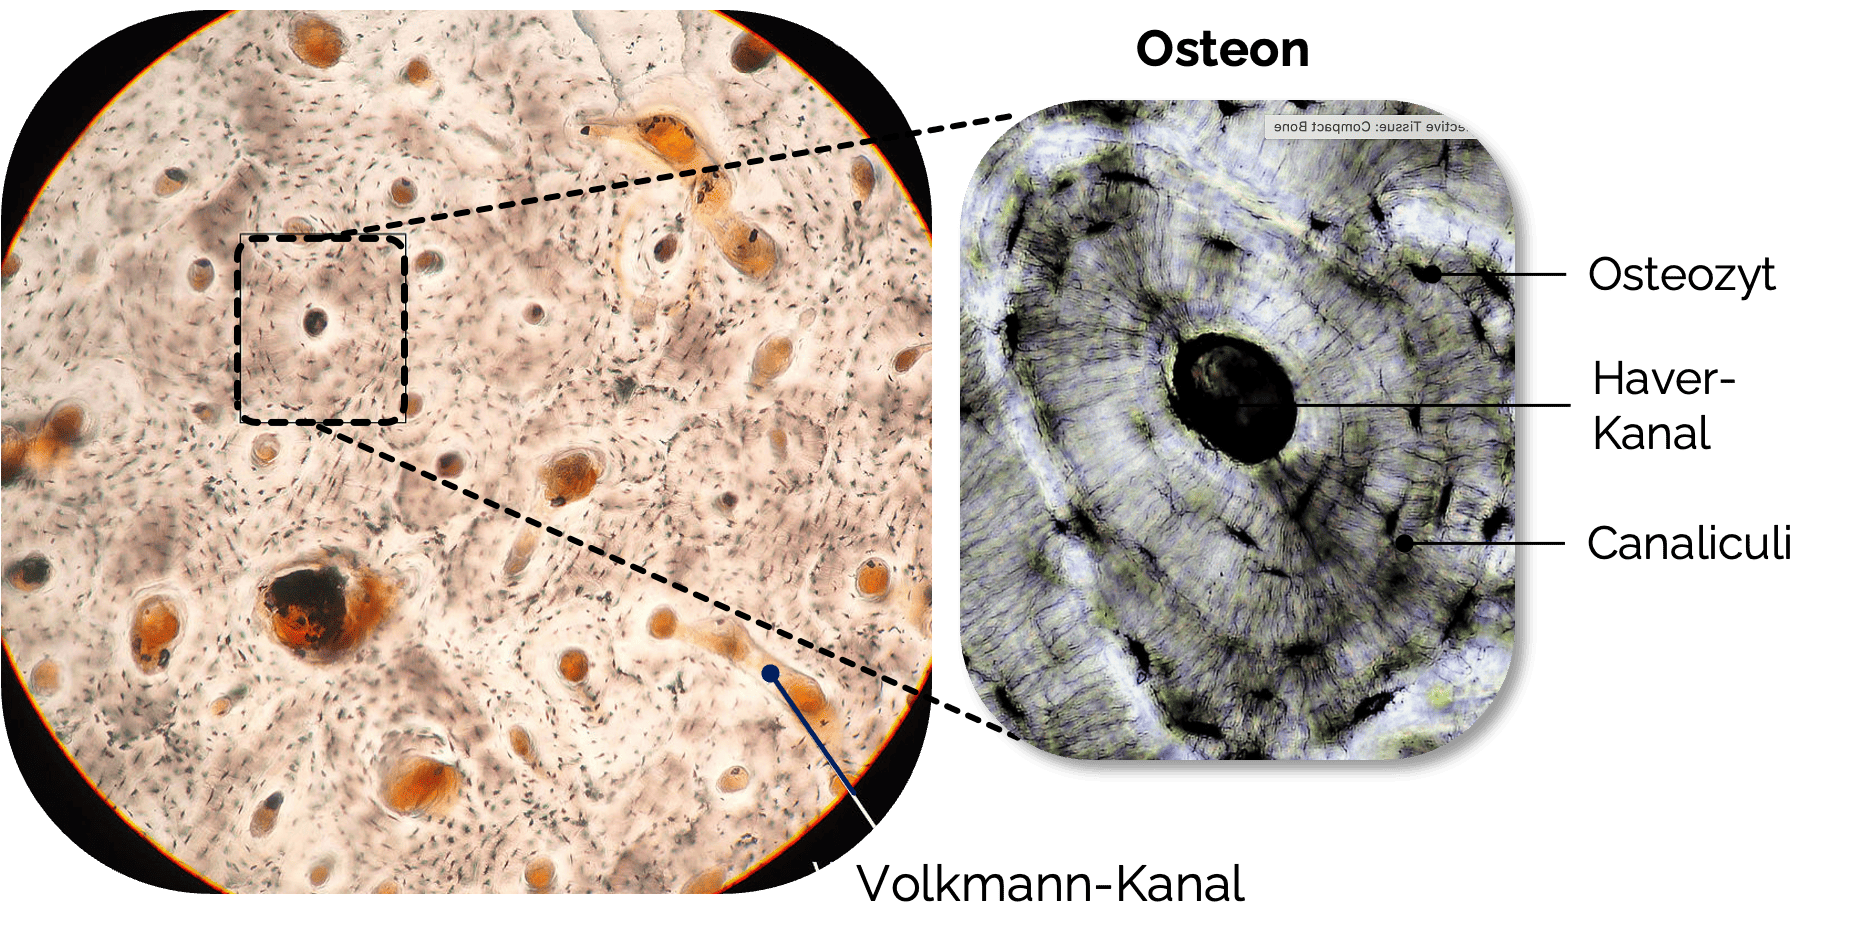

Substantia compacta (Kompakta ):

- Bestandteil des Lamellenknochens (häufigster Knochentyp)

- Bildet die äußere Knochenrinde (auch Kortikalis

genannt) unterhalb des Periosts - Die Substantia compacta

besteht aus dicht gepackten Knochenlamellen, die in konzentrischen Strukturen angeordnet sind (Osteone) - Steht mit dem roten Knochenmark der Spongiosa

in Verbindung

- Überzieht die Binnenräume des Knochens, d.h. die

Spongiosatrabekel, Havers und Volkmannkanäle - Besteht aus nicht-mineralisierten Kollagenfibrillen